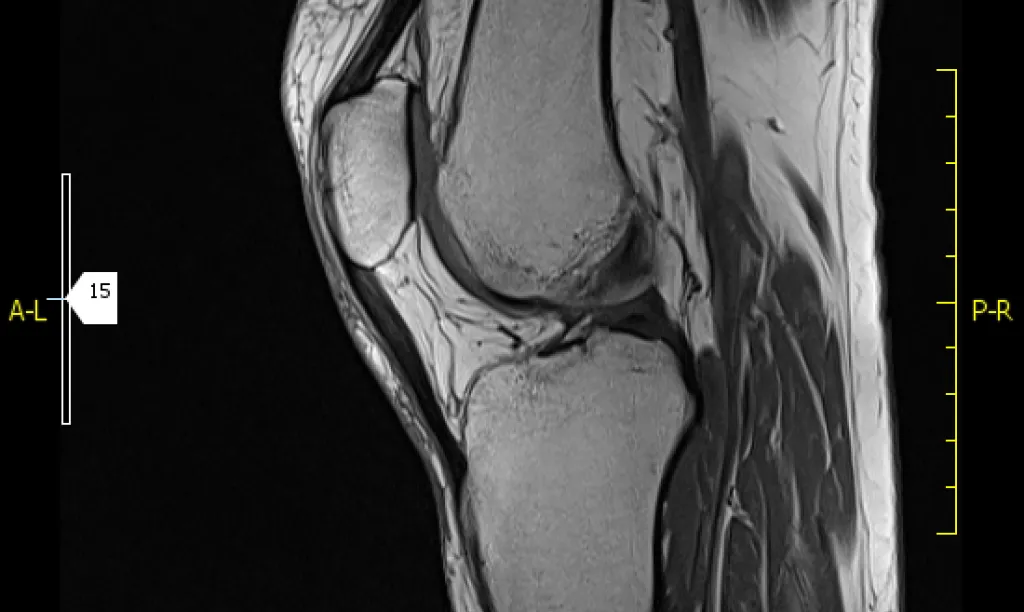

Resonancia magnética de rodilla

La Resonancia Magnética de rodilla es la prueba de elección para valorar meniscos, ligamentos cruzados, cartílago, músculos y estructuras óseas.

¿Para qué sirve?

La Resonancia Magnética se utiliza para valorar distintas enfermedades que su médico, tras una correcta exploración clínica y física, puede sospechar que tiene. Las más habituales son:

1. Lesiones meniscales: roturas o degeneración meniscal

2. Lesiones de ligamentos: rotura de ligamento cruzado anterior o esguince de distinto grado

3. Lesiones musculares y tendinosas: roturas fibrilares, desgarros musculares, tendinitis

4. Lesiones de cartílago: artrosis, desgaste cartílago femoropatelar (condropatía femoropatelar)

5. Fracturas óseas que podrían no ser detectadas por rayos X u otros exámenes por imágenes

6. Valoración de sinovial: derrame articular, sinovitis

7. Infecciones articulares y óseas: Artritis y osteomielitis

8. Tumores (originados en hueso o metástasis)

9. Necrosis ósea

10. Controles postcirugía